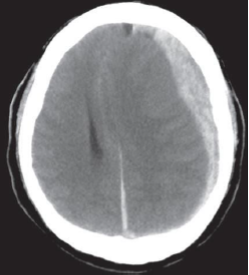

Um homem de 77 anos foi levado ao prontosocorro pelo Serviço de Atendimento Móvel de Urgência, sem resposta, após uma queda de mesmo nível. Na admissão, estava sonolento, não obedecia a comandos e apresentava paralisia de 3º nervo craniano esquerdo, com midríase. Ele tinha histórico de fibrilação atrial. A seguir está sua Tomografia Computadorizada de crânio. Qual das seguintes alternativas corresponde à melhor intervenção terapêutica?